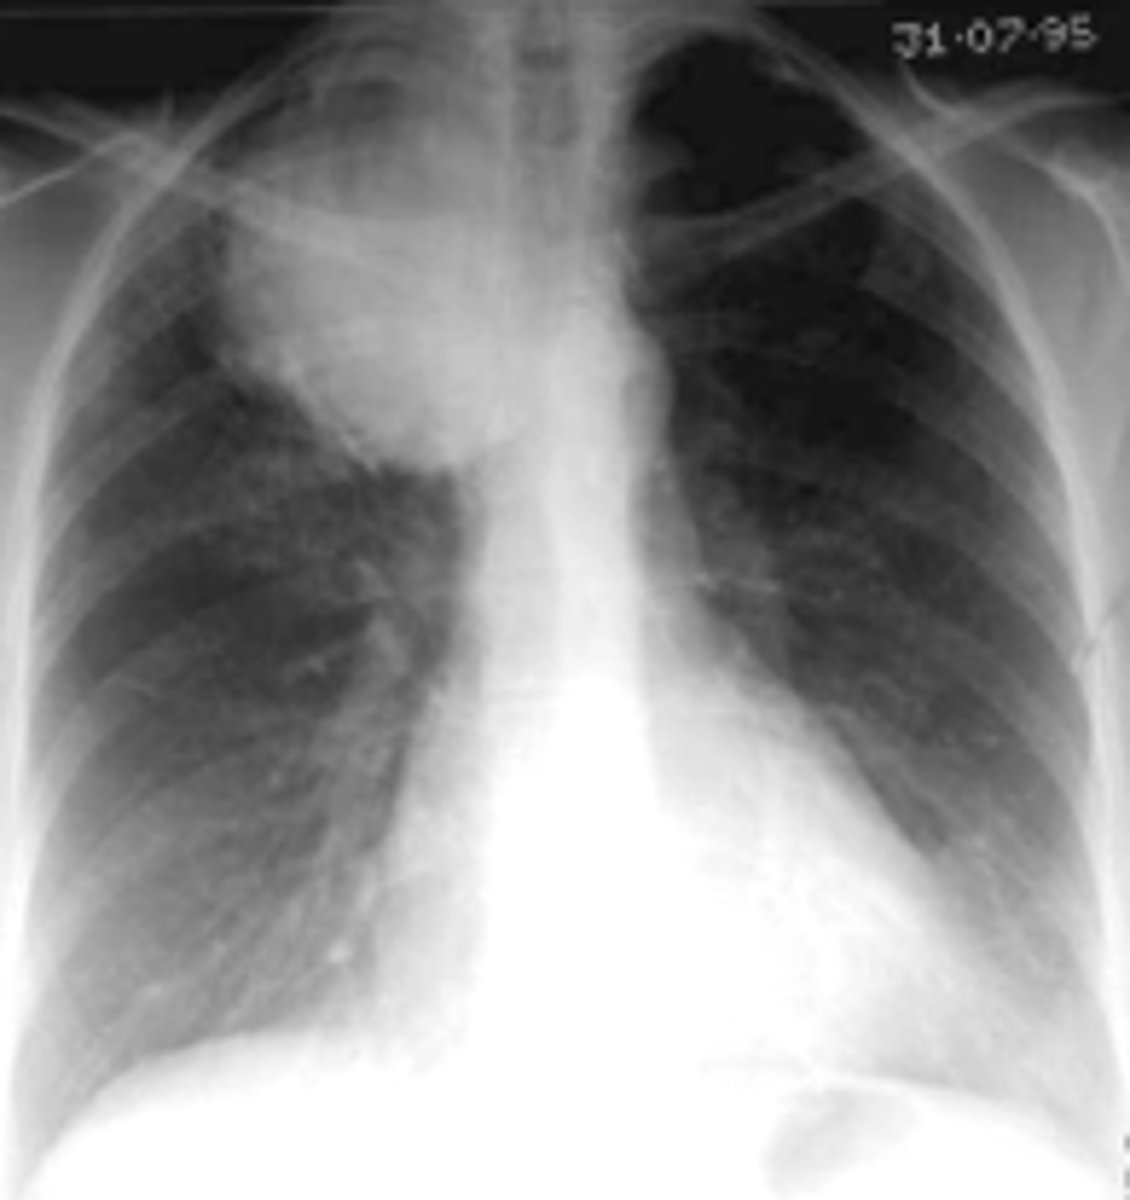

Common x-ray finding of primary active TB

oEnlargement of hilar or mediastinal lymph nodes is present about 95% of the time in primary active TB.

oCalcification usually occurs at the site of infection or in the node or both.

<p>oEnlargement of hilar or mediastinal lymph nodes is present about 95% of the time in primary active TB.</p><p>oCalcification usually occurs at the site of infection or in the node or both.</p>